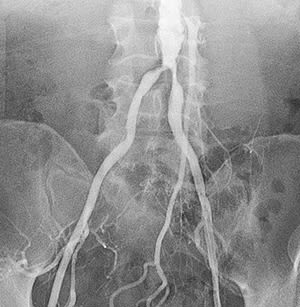

Peripheral angiography is a test that uses X-ray and dye (contrast material) to map the blood vessels (arteries) in your lower body, legs, and arms. This map can show where blood flow may be blocked.

Angiogram of abdominal aorta and iliac arteries.